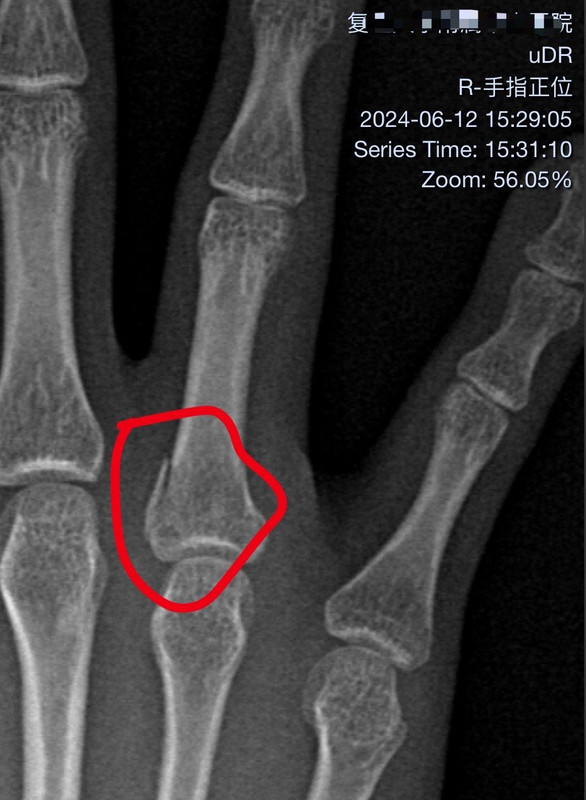

好家伙,抽了12管血。喝多了不小心摔了一下,把手指整骨折了,无名指,一点点,伤了韧带。明天手术,主任博导亲自操刀,师从顾玉东院士。相信专家。我的纤纤玉手一定完好如初。[doge]